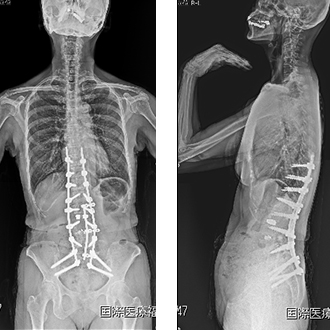

2. 成人脊柱変形に対する変形矯正手術

脊柱変形矯正手術は、脊椎外科の中でも最も難易度の高い手術のひとつとして位置づけられています。当院では脊柱変形疾患における代表的手術である脊柱変形矯正手術に取り組んでいます。近年ではLLIF(5.を参照してください)といわれる固定術が導入され手術が低侵襲化され、80歳代の高齢の方でも条件が合えば手術を選択することが出来るようになりました。

手術によって前傾姿勢が改善して問題なく歩行ができるようになりました。